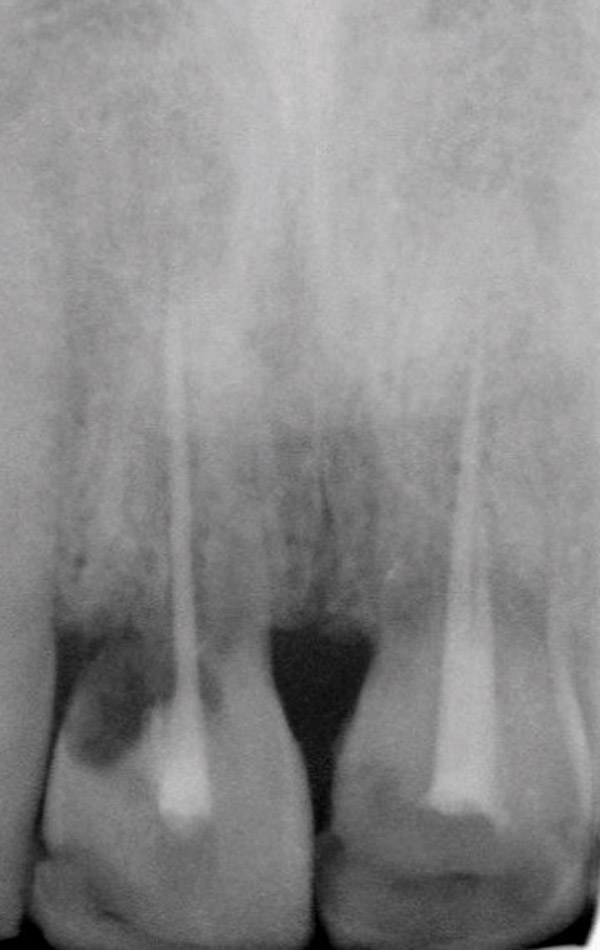

Figure 9: Initial view of resorbed maxillary central incisors.

Figure 9

Figure 14  Initial periapical radiograph revealed internal root resorption of teeth Nos. 8 and 9 with almost complete horizontal severing of the crowns from the roots.

Figure 14

Figure 15  After extraction and 3 months of healing, two implants were placed in ideal position and with primary stability at sites Nos. 8 and 9. Implants were stable. Dehiscence defects exposing 13 threads were produced.

Figure 15